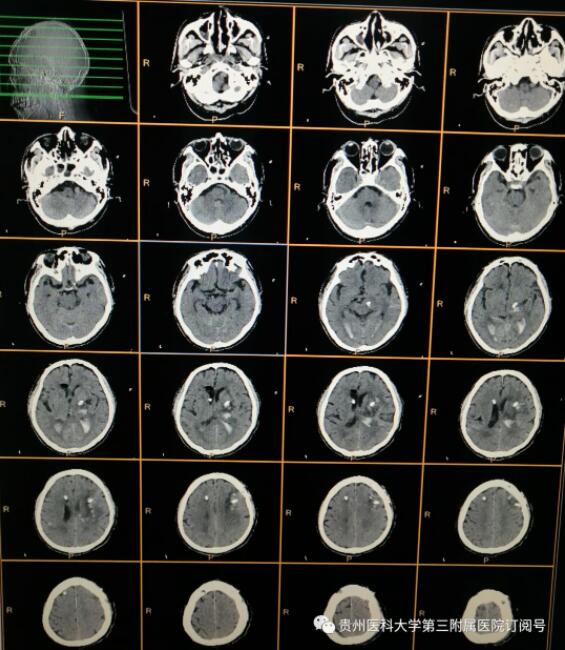

术后复查头颅CT:颅内血肿基本清除

术后第七天,患者意识逐渐好转,左侧肢体可自主活动,能配合医师完成相关动作,右侧肢体在刺痛状态下可水平移动。目前患者仍在神经外科康复治疗中。